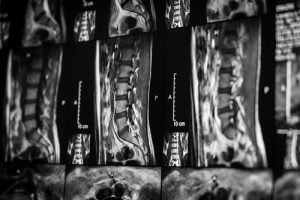

Единственным достоверным показателем прочности кости является плотность костной ткани. Ее невозможно измерить с помощью стандартного рентгена (он чаще применяется для диагностики переломов), но, существует специализированный низкодозный рентгеновский тест, который называется костная денситометрия. Его можно использовать для измерения плотности костной ткани в различных частях скелета.

Немецкие клиники располагают необходимым современным оборудованием для быстрой и качественной диагностики остеопороза. DXA – двухэнерегетическая рентгеновская абсорбциометрия – это методика, позволяющая обнаружить даже небольшой процент потери костной ткани. Она является наиболее распространенным тестом для диагностики остеопороза. Дополнительно могут использоваться:

- QCT (количественная компьютерная томография). Измерение проводится на позвоночнике или бедре.